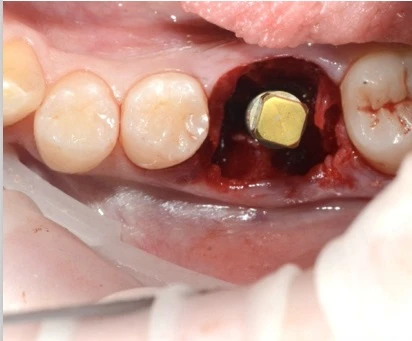

Наши работы